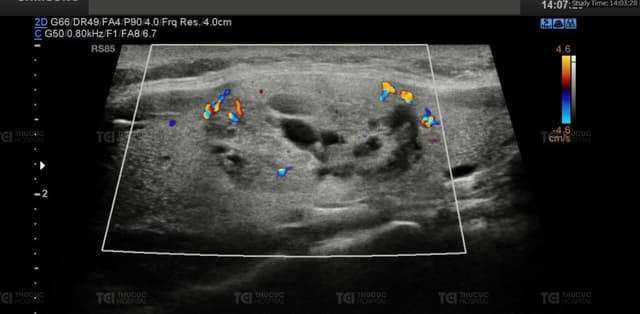

Nhân giảm âm tuyến vú có gây nguy hiểm?

Nhân giảm âm tuyến vú là thuật ngữ không mới nhưng vẫn khá lạ lẫm với nhiều bệnh nhân lần đầu tiếp cận. Vậy nhân giảm âm tuyến vú là tình trạng như thế nào, có gây nguy hiểm? Hãy cùng Thu Cúc TCI tìm hiểu. 1. Hiểu về nhân giảm âm tuyến vú Nhân […]